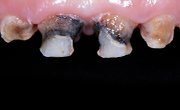

Our crowns are crafted with unmatched accuracy using the latest digital technology, ensuring a perfect fit and superior functionality for every patient.

We use only the finest materials ensuring that every crown offers exceptional strength, wear resistance, and a natural appearance.